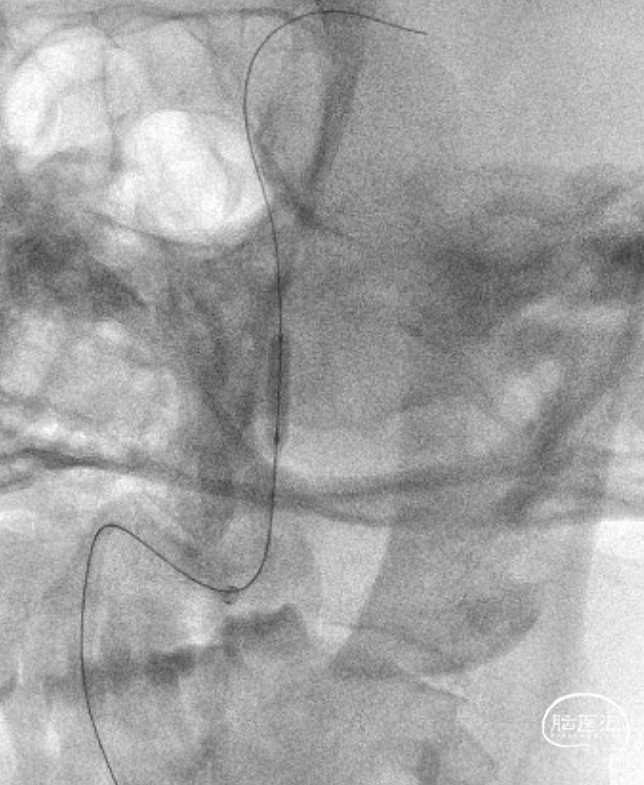

赛诺Neuro LPS®颅内球囊扩张导管 2.75*15mm

赛诺NOVA®颅内药物洗脱支架 2.75*12mm

赛诺NOVA®颅内药物洗脱支架 2.75*12mm输送至病变段。

10atm压力释放赛诺NOVA®颅内药物洗脱支架。